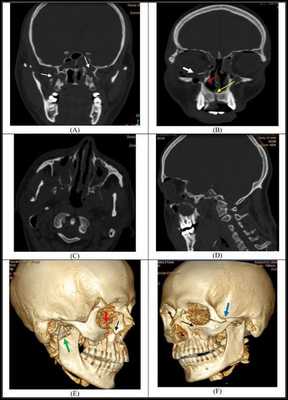

Данные клинической картины необходимо подтвердить результатами рентгенологического исследования. Рентгенограммы позволяют уточнить топическую диагностику перелома, выраженность смещения отломков, наличие костных осколков, отношение корней зубов к щели перелома. Обычно делают два рентгеновских снимка: в прямой и боковой проекциях, или ортопантомограмму. При переломах мыщелкового отростка дополнительную информацию дают специальные укладки для ВНЧС.

Рентгенограмма нижней челюсти в боковой проекции при её переломе в области угла: незначительное смещение отломка вследствие наличия зуба мудрости на меньшем отломке

Рентгенограмма нижней челюсти в боковой проекции при её переломе в области угла и отсутствии зубов на меньшем отломке: значительное смещение меньшего отломка вверх до соприкосновения альвеолярной части с коронкой зуба мудрости

Рентгенограмма нижней челюсти в прямой проекции. Перелом мыщелкового отростка со смещением кнаружи

Варианты расположения плоскостей при переломе нижней челюсти